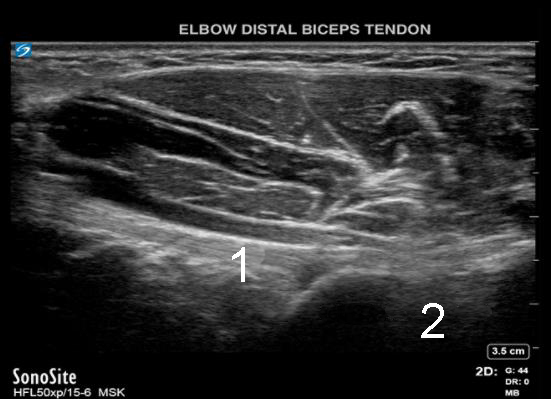

Codo: Inyección distal en tendón de bíceps 2 - Imagen

Tendón bíceps

Tuberosidad del radio